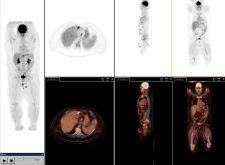

Last year, however, Philips Medical Systems introduced the Gemini TF PET/CT, which provides what Philips calls TruFlight, its own version of TOF technology. The Gemini TF is a high-performance, fully 3-dimensional, time-of-flight PET scanner combined with a Brilliance CT scanner (currently up to 64-slices). The PET scanner uses lutetiumyttrium oxyorthosilicate (LYSO) crystals that are placed in an Anger-logic detector, accomplishing a light spread in the detector that is uniform. The scanner was designed by Philips to be used as a high-performance conventional PET scanner in its own right, as well as a TOF scanner to provide improved timing resolution.

“TruFlight is a very sophisticated stopwatch,” said Dr. Osman. “Philips’ time-of-flight technology measures the actual time difference between the detection of two simultaneous and almost coincident gamma rays. This difference in detection times of the gamma rays observed by the PET scanner is used to more accurately localize the annihilation origin. It is the improvement in event localization that ultimately reduces image data noise, producing a higher quality image, allowing for lower tracer dose amounts in patients and shorter imaging times.”

Since the introduction of the Gemini, Suleman Surti, Ph.D., research assistant professor at the University of Pennsylvania, has led a study to evaluate its intrinsic TOF capability and its impact on the reconstructed images. Dr. Surti and his fellow researchers “performed experiments with this scanner using reproducible phantoms mimicking the presence of lesions in a patient.” The measurement capability of the new TOF scanner, when used to reconstruct an image, showed improved image quality and, in turn, allowed for more accurate detection of small lesions. The study concluded that “[t]his new time-of-flight scanner, used with LYSO detector crystals, will improve the diagnostic accuracy of images, potentially leading to improved sensitivity and specificity in cancer lesion detection tasks in heavy patients.” However, Dr. Surti also mentioned, “Our data indicates that more robust measures are needed to fully quantify the gains in imaging quality and to better define the relationship of image quality to patient size and timing resolution.”